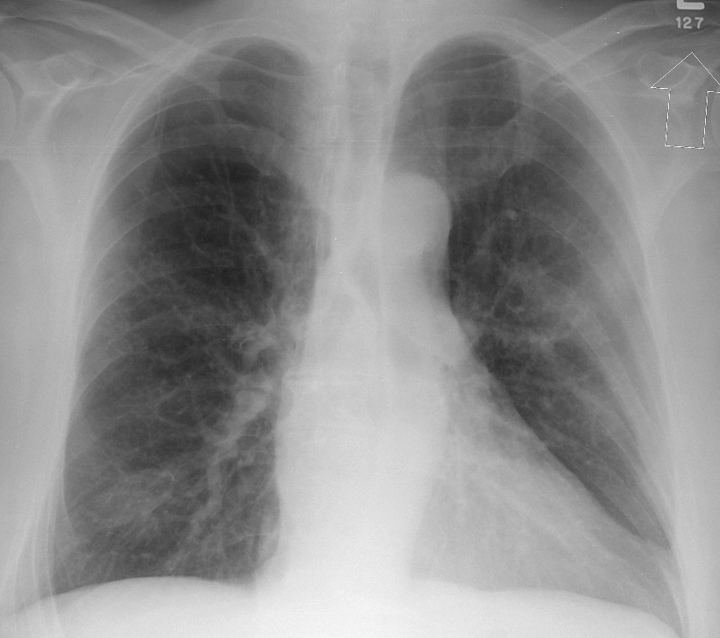

Case 1 PA

Peric calcification